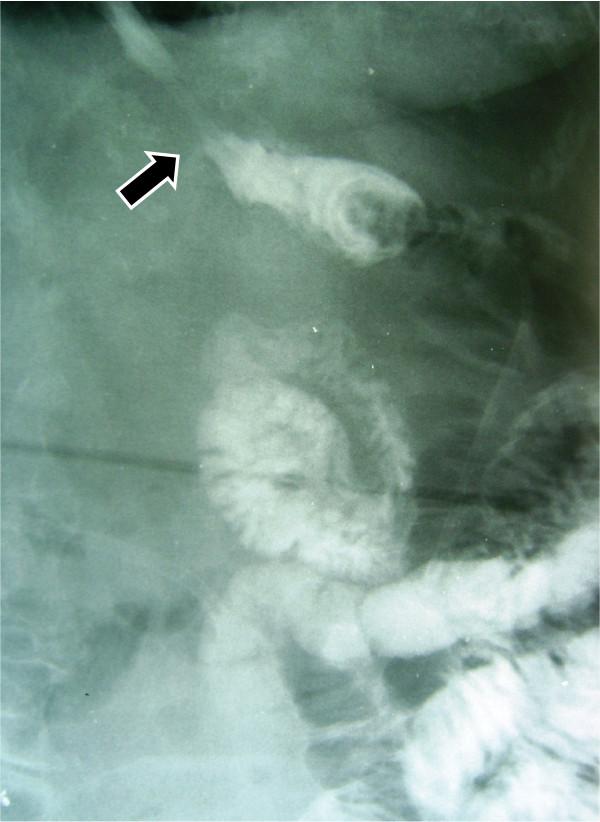

Between January 2004 to December 2008, 588 consecutive patients with a proven diagnosis of gastric cancer were taken to the operation room to try a curative treatment. Of these, 173 underwent total gastrectomy, 9 of them had esophagojejunal fistula (5.2%). In three selected patients a trans-anastomotic naso-enteral feeding tube was placed under fluoroscopic vision when the fistula was clinically detected and a complete polymeric enteral formula was used.

The complete closing of the esophagojejunal fistula was obtained in day 8, 14 and 25 respectively.